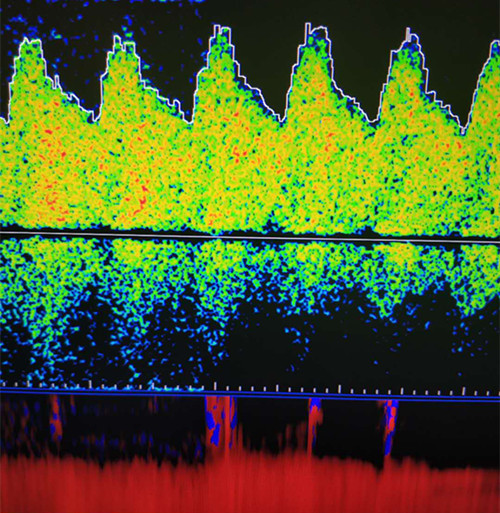

前循環(huán)動脈低波動表現(xiàn)